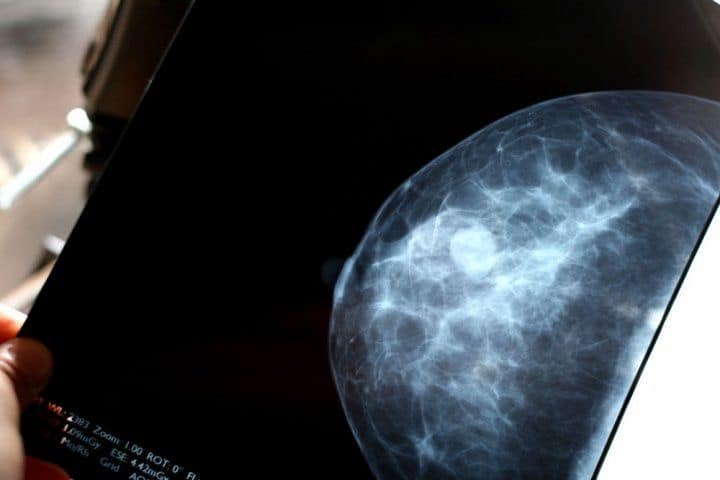

یک توده سرطان سینه ممکن است احساس گرد، نرم و لطیف داشته باشد و میتواند در هر نقطهای از سینه ایجاد شود.معاینات فردی تا تشخیص سرطان سینهآخرین دستورالعملهای انجمن سرطان آمریکا (ACS) نشان میدهد که معاینات فردی، مخصوصاً برای زنانی که ماموگرافی غربالگری را انجام میدهند، و یا حتی وقتی پزشکان این آزمایشات را انجام میدهند فواید، آشکاری حاصل نشده است، هنوز هم برخی از مردان و زنان وجود دارند که به سرطان سینه مبتلا میشوند و علائم آن را در خود مییابند.اگر زن هستید، مهم است که با ظاهر سینه خود آشنا شوید و آنها را مرتباً بررسی کنید. این کار به شما کمک میکند تا از هرگونه تغییر یا ناهنجاری در هنگام وقوع آگاه شوید. زنان برای سلامتی خود باید چکاپ روتین داشته باشند که معاینه منظم سینهها از مهمترین موارد آن است.یک توده سرطان سینه چه حسی دارد؟موارد توده سرطان سینه، احساس یکسانی ندارند. پزشک شما باید هر نوع تودهای را بررسی کند، خواه با رایجترین علائم ذکر شده در زیر مطابقت داشته باشد یا نداشته باشد.معمولاً یک توده سرطان سینه:یک توده سخت استبدون درد استدارای لبههای نامنظم استبیحرکت است (هنگام هل دادن حرکت نمیکند)در قسمت فوقانی پستان شما ظاهر میشودبا گذشت زمان رشد میکندهمه موارد توده سرطان سینه از این معیارها برخوردار نیستند و توده سرطان سینه که همه این صفات را داشته باشد، توده عادی نیست. یک توده سرطان سینه ممکن است احساس گرد، نرم و لطیف داشته باشد و میتواند در هر نقطهای از سینه ایجاد شود. در بعضی موارد، توده سرطان سینه حتی میتواند دردناک نیز باشد.برخی از خانمها همچنین بافت متراکم و الیافی پستان دارند. که در این صورت، احساس توده سرطان سینه یا تغییر در سینه ممکن است دشوارتر باشد.داشتن سینههای متراکم نیز تشخیص سرطان سینه را در ماموگرافی دشوارتر میسازد. با وجود داشتن بافت سختتر، هنوز هم میتوانید به محض وقوع تغییر در پستانها، آن را تشخیص دهید.

توده سرطان سینه بیحرکت است. این توده اغلب منجر به سرطان سینه میشود.وزن. اضافه وزن یا چاقی خطر ابتلا به سرطان پستان را افزایش میدهد.بیماری خوش خیم پستان. برخی از بیماریهای خوش خیم (غیر سرطانی) پستان ممکن است خطر ابتلا به سرطان پستان را در آینده تحت تأثیر قرار دهد.استفاده از هورمون. اگر از درمان جایگزینی هورمون (HRT) استفاده کرده باشید یا در حال حاضر از آن استفاده میکنید، احتمال ابتلا به سرطان پستان بیشتر است.سابقه قاعدگی. دوره قاعدگی زودرس (قبل از ۱۲ سالگی) ممکن است خطر ابتلا به سرطان پستان را افزایش دهد.اواخر سن یائسگی. تاخیر در یائسگی (بعد از ۵۵ سالگی) ممکن است شما را در معرض هورمونهای بیشتری قرار دهد، که میتواند ریسک ابتلای شما را افزایش دهد.بافت متراکم سینه. مطالعات نشان میدهد زنانی که بافت پستان متراکمی دارند، احتمال ابتلا به سرطان در آنها بیشتر است. این بافت ممکن است تشخیص سرطان را نیز دشوارتر سازد.سبک زندگی کم تحرک. زنانی که به طور منظم ورزش نمیکنند، بیشتر از زنانی که اغلب اوقات ورزش میکنند دچار سرطان پستان میشوند.مصرف دخانیات. سیگار کشیدن خطر ابتلا به سرطان پستان را به ویژه در زنان جوان که هنوز یائسه نشدهاند، افزایش میدهد.مصرف الکل. به ازای هر نوشیدنی الکلی که مصرف میکنید، خطر ابتلا به سرطان پستان افزایش مییابد. تحقیقات نشان میدهد که نوشیدن مقداری الکل مشکلی ندارد، اما استفاده زیاد از الکل با خطر بالاتر سرطان پستان در ارتباط است.